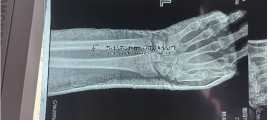

術(shù)前影像術(shù)前影像術(shù)中透視術(shù)中透視術(shù)中透視術(shù)中透視安裝外架術(shù)后外觀及影像術(shù)后外觀及影像術(shù)后外觀及影像本文轉(zhuǎn)載自好大夫平臺:···